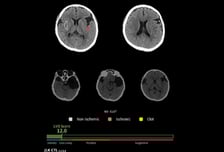

제이엘케이, AI 솔루션 'JLK-CTL' 혁신의료기기 통합심사 통과

의료 인공지능(AI) 전문기업 제이엘케이가 AI 기반 뇌졸중 분석 솔루션 'JLK-CTL'이 식품의약품안전처의 혁신의료기기 통합심사를 통과했다고 28일 밝혔다. JBS-01K, JLK-LVO에 이은 세 번째 성과다. 제이엘케이는 이번 승인에 따라 비조영 CT 기반 AI 진단 영역의 기술력을 입증하며 향후 혁신의료기기 인증 솔루션 패키지 공급을 통한 사업 확장 가능성을 한층 높이게 됐다고 자평했다. 앞서 지정받은 JBS-01K, JLK-LVO 등과 함께 비조영 CT, CTA, DWI(확산 강조 영상) 등 뇌졸중 진단에 필수적인 영상 분석에 비급여 처방을 할 수 있는 AI 솔루션 '3종 패키지'를 완성하게 됐다는 것. JLK-CTL은 조영제 없이 촬영한 비조영 CT(NCCT) 영상으로 대혈관 폐색 여부를 신속하고 정확하게 예측하는 AI 솔루션이다. 응급 현장에서 주로 쓰이는 비조영 CT를 기반으로 조기에 대혈관 폐색 의심 환자를 선별해 골든 타임을 확보한다. 이어지는 CTA, DWI